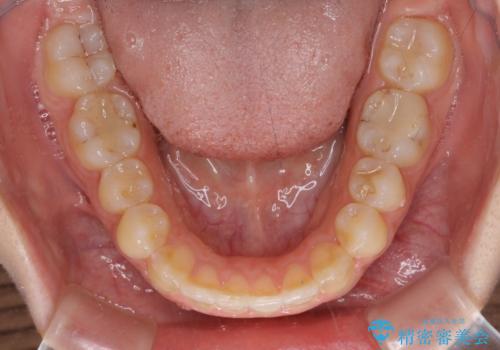

前歯のデコボコの解消と並行して上下の奥歯を圧下させるようにすることで、前歯を接触させるように計画しました。

上下の隙間に舌が入り込むことがオープンバイトの原因であったため、舌の筋肉のトレーニングも並行して行い、後戻りの抑制を図りました。